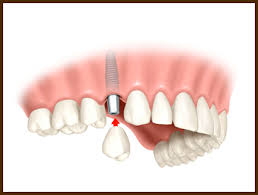

- Kada nedostaje jedan ili vise zuba